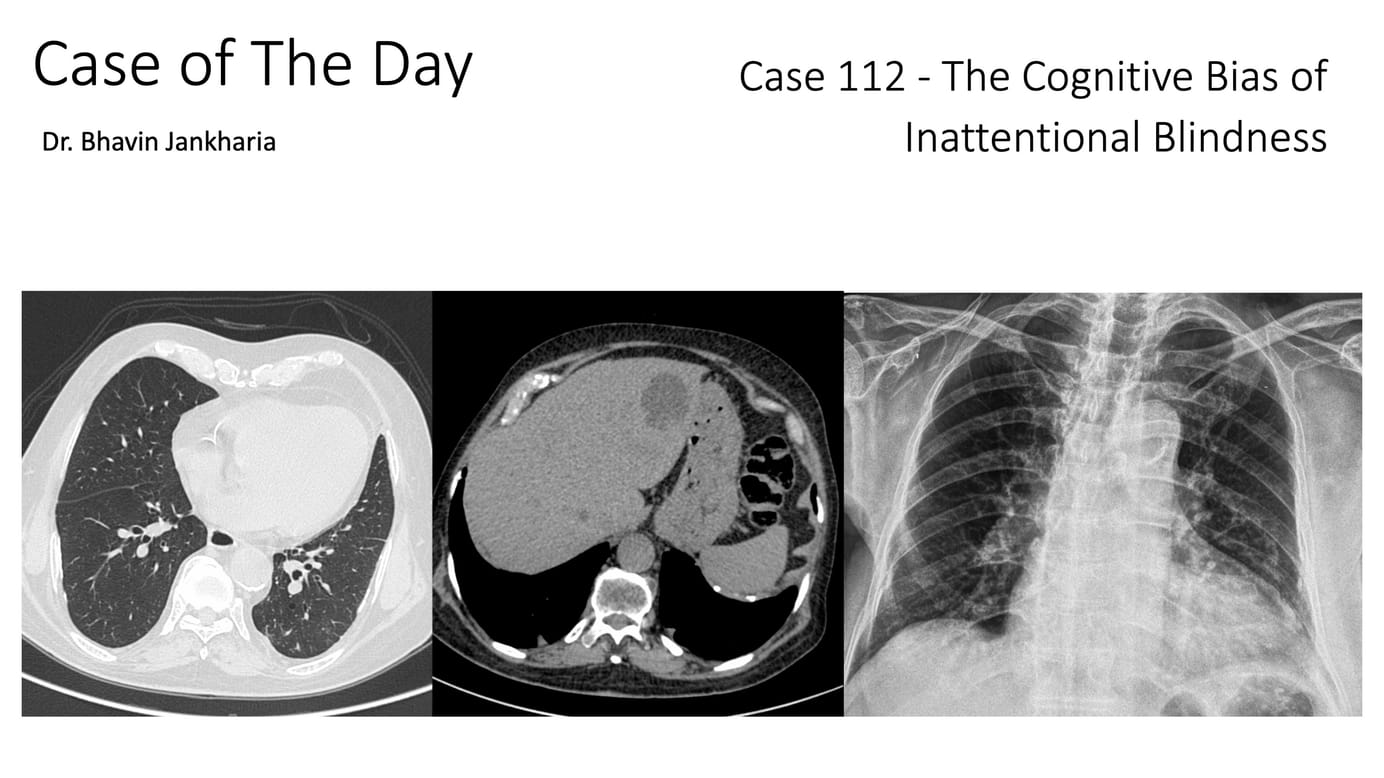

Case of the Day 112 - The Cognitive Bias of Inattentional Blindness

82 yrs old cough and fever for 1 month.

The video describes the case, asks you to spot the findings and then describes the pathology with other examples and then tries to understand why these findings were missed by multiple radiologists over multiple years, likely due to the cognitive bias of inattentional blindness.